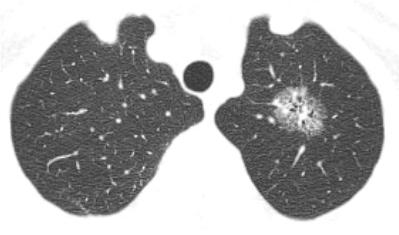

近日,62岁的王女士在北京中医药大学东方医院秦皇岛医院(秦皇岛市中医医院)体检时,发现左上肺有磨玻璃阴影(肺结节),提示“恶性不除外”。患者及家属非常紧张焦虑,慕名找到在肺病科出诊的北京中医药大学东方医院秦皇岛医院副院长马建岭主任医师。经过分析检查资料,考虑患者恶性病变的可能性较大,但明确诊断还需进一步活检取病理。由于该结节靠近肺尖(外周),损伤小的普通电子气管镜难以到达病变部位,若采用经皮肺穿刺则创伤偏大,可能会导致患者出现气胸、出血的情况。

左肺尖磨玻璃结节

纠结之际,马建岭主任医师与秦皇岛市中医医院肺病科副主任丁静又仔细查看了患者胸部CT的薄层图像,发现有一个特别小的支气管可以通到结节处。但由于该结节处于外周,从气管过去路程较长,且支气管分叉较多,为确保活检灶部位精确无误,专家们详细手绘了导航图,并使用4.2mm的超细气管镜,结合最新引进的清醒镇静等无痛麻醉技术,为患者舒适、顺利地完成了电子支气管镜检查,最终病理结果为腺癌。